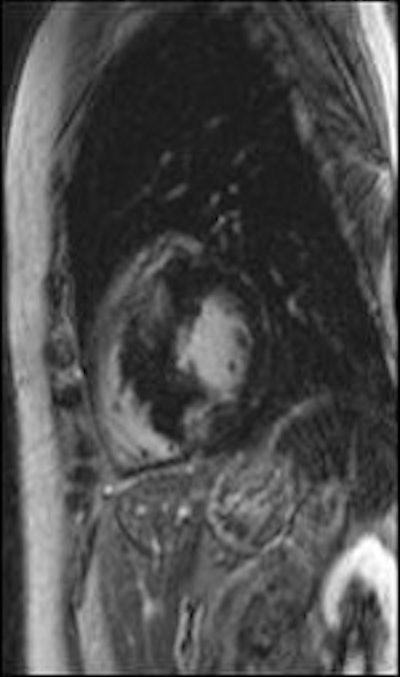

Late gadolinium enhancement shows focal myocardial fibrosis. All images courtesy of Dr. Daniel Theisen.

Late gadolinium enhancement's prognostic capacity for hypertrophic cardiomyopathy, a cause of sudden death in young athletes, is significant. Citing last year's study by Dr. Rory O'Hanlon, of London's Royal Brompton and Harefield NHS Foundation Trust (Journal of the American College of Cardiology, 7 September 2010, Vol. 56:11, pp. 867-874), Theisen explained that the 217 patients were divided into two groups: those showing late gadolinium enhancement and those not. Patients in the former group were more likely to reach the primary end point of sudden cardiac death and sustain ventricular tachycardia or ventricular fibrillation. Thus, focal myocardial fibrosis detected by late gadolinium enhancement has proved to be an independent predictor of adverse outcome.

"It is not entirely clear whether these patients with focal myocardial fibrosis in late gadolinium enhancement will benefit from early antifibrotic therapy or ICD implantation in the future," he said.